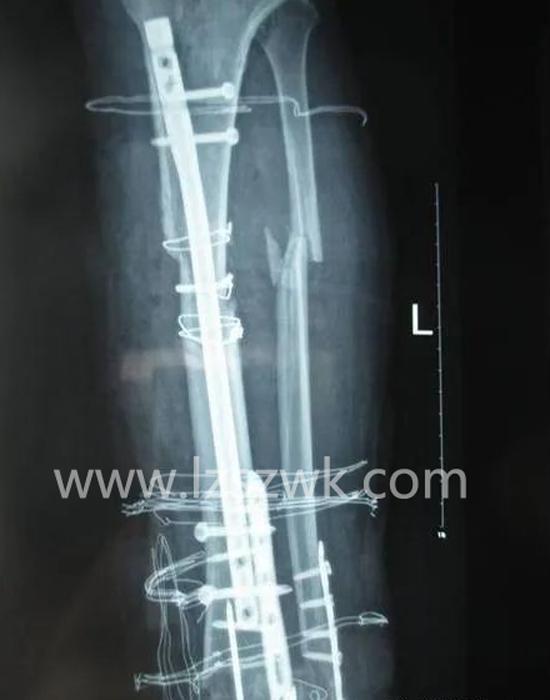

在大段骨缺损治疗过程中,促进骨愈合的首要条件是稳定骨折断端,既往常使用钢板固定骨折断端,但钢板固定剥离软组织及骨膜范围广泛,对骨缺损部位的血运破坏更大,且易造成植骨段螺钉松动和钢板断裂。交锁髓内钉联合骨移植技术目前已广泛应用于骨缺损的临床治疗上,该技术选择交锁髓内钉这一“生物性内固定”方式,维持骨缺损部位的稳定性,并将植骨材料填充于缺损处,进一步加强了骨折断端之间的稳定性,保留了骨传导性,同时对新生骨痂有诱导成骨作用,加快了骨缺损修复速度,提高愈合率,有文献报道曾使用交锁髓内钉联合骨移植修复长达15cm骨缺损。